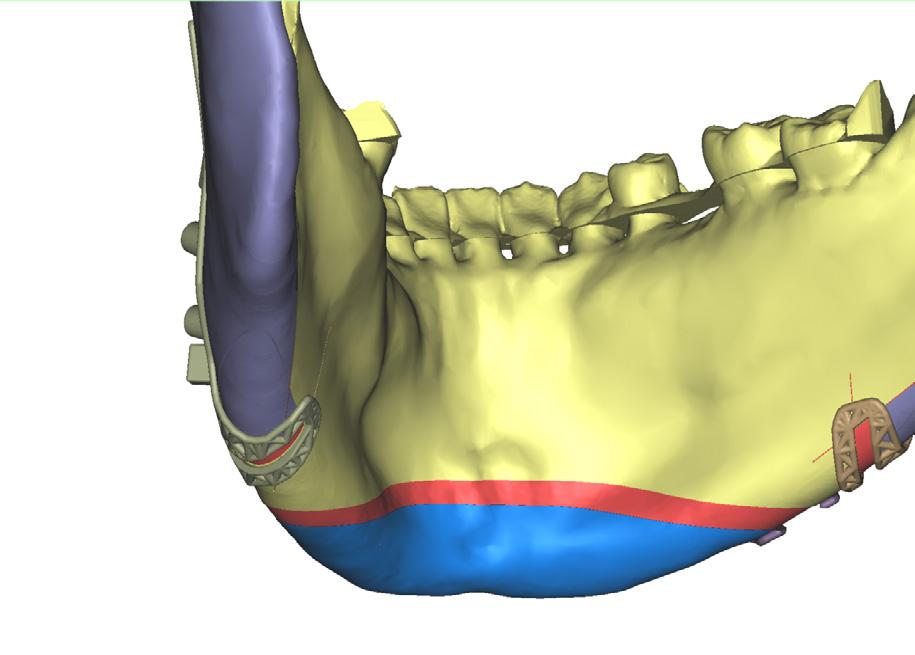

Computer-guided customised treatment of unilateral condylar hyperplasia by proportional condylectomy and orthognathic surgery

Wang D, Smit R, Harrison J and Sealey C

Primary inferior alveolar nerve protection: a CAD/CAM approach

Betar N, Badri D, McCombe A and Finn B